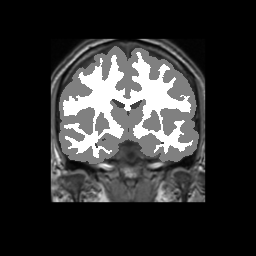

Accuracy is reported as Dice overlaps between a tool's segmentation and the Internet Brain Segmentation Repository (IBSR) manual segmentation for each of the 18 IBSR subjects. The inter-tool comparison (on the left below) shows the median Dice coefficient for each tissue class. The overlaps for FSL (from which the median values are drawn) are shown in the plot on the right.

Subject Accuracy (IBSR)

Overlap coefficients for each tissue class are shown here for each IBSR subject. Select a subject below to see the FSL results compared to other tools.